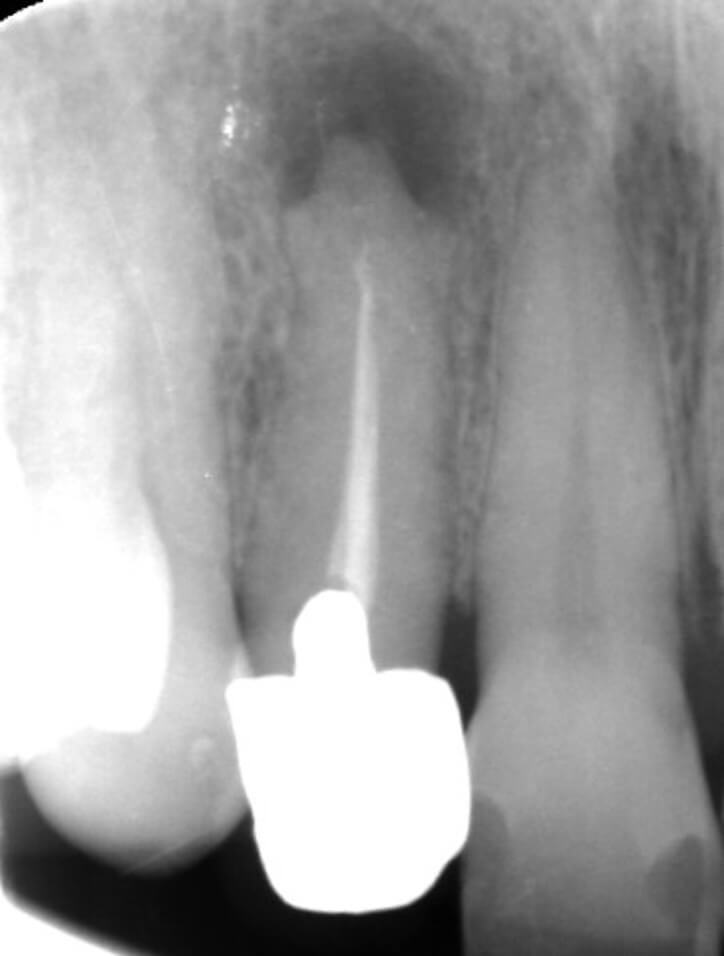

3,根尖性歯周炎;根尖性歯周炎とは歯の神経をとった歯に起きる、歯根の先端から細菌が周囲の骨や組織に感染して炎症や膿がたまる病気です。根尖性歯周炎では、普段は腫れや痛みがない事が多いです。しかし、体調不良や免疫力が低下した時には歯自体が何もしていなくてもズキズキ痛む、歯茎や顔が腫れるといった強い痛みや腫れが出ることがあります。根尖性歯周炎の腫れの特徴としては抗生物質を服用するか、もしくは根管治療を行わなければ絶対に治ることはありません。